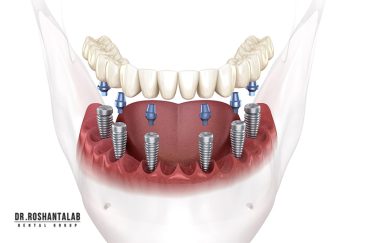

🔸کاشت ایمپلنت فلپ لس یا بدون جراحی و بدون بخیه زیر سه دقیقه

🔸 کاشت دندان یک روزه ( کشیدن و کاشت همزمان )

🔸جراحی پیشرفته نظیر سینوس لیفت

انتخاب بهترین متخصص ایمپلنت که به تکنیکهای روز دنیا مسلط باشد، تضمینکننده سلامت فک و زیبایی لبخند شماست. در کلینیک دندانپزشکی دکتر روشنطلب، ما با بهرهگیری از تجهیزات دیجیتال در ۵ شعبه فعال (تهران، اصفهان، رشت و استانبول ترکیه)، خدمات تخصصی کاشت ایمپلنت دندان را برای بیمارانی که کیفیت و دقت برایشان اولویت دارد، ارائه میدهیم. در این متد، پروسه درمان با ظرافت بالا انجام شده؛ راهکاری ایدهآل برای کسانی که به دنبال درمان بدون درد با بالاترین نرخ موفقیت هستند.